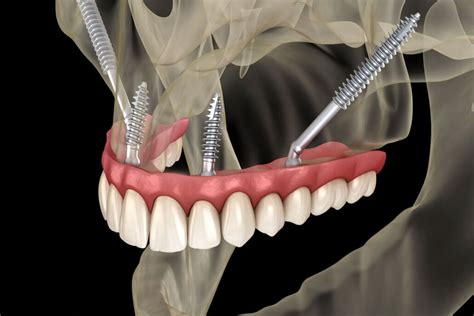

La principal diferencia entre los dos tipos de implantes dentales es la longitud y el espacio anatómico donde se colocan. Los implantes cigomáticos son más largos de los implantes convencionales, miden entre 35 y 55 mm de largo.

Para que la intervención sea exitosa, los implantes dentales deben anclarse en la mandíbula superior, cerca del hueso cigoma denso. Estos tornillos de hasta 52 milímetros llegan hasta el hueso de la mejilla para garantizar la resistencia y durabilidad.

La intervención quirúrgica para colocar los implantes cigomáticos comienza con la realización de una pequeña incisión en las encías del paciente para llegar a la mandíbula. Se coloca el implante de forma que roza o atraviesa los senos nasales y queda anclado al hueso cigomático. Actualmente los Dres. Peñarrocha colocan los implantes cigomáticos con cirugía guiada. Esto aumenta la precisión en la ubicación del éxtremo de dichos implantes, que se colocan en una zona no demasiado alejada del ojo. Este tipo de cirugía se realiza bajo anestesia general o sedación consciente intravenosa y anestesia local.

Este tipo de implantes permite, en muchas ocasiones, que el especialista coloque la prótesis fija provisional de forma inmediata (carga inmediata). Así pues, el paciente puede gozar de su dentadura fija el mismo día en el que se le practica la intervención. La decisión definitiva va a depender de la correcta estabilidad de los implantes que se alcance durante la cirugía, lo cual a su vez depende del hueso del paciente. Lo que solemos hacer es tener previamente toda la información digital necesaria para realizar la prótesis de carga inmediata y si se confirma que los implantes quedan estables, el laboratorio comienza a fabricar la prótesis fija provisional en cuanto termina la cirugía.